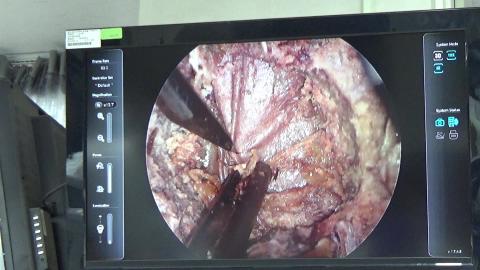

蛋白質: IEC, chromatofocusing & hydroxyapatite chromatography - 中文版

蛋白質: IEC, chromatofocusing & hydroxyapatite ... 觀看(2083)